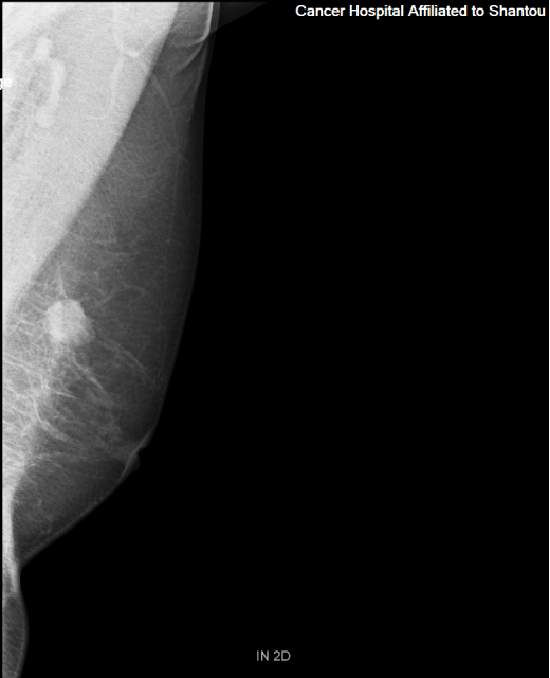

患者李女士(化名)在外院确诊为乳腺癌,这一消息让她及家人陷入巨大的焦虑与无助。经过多方咨询,李女士前来我院乳腺外科张永渠副主任门诊就诊。

乳腺钼靶.png

乳腺钼靶

经过对患者身体状况的全面评估,并了解到患者对切除乳房的担忧和恐惧后,张永渠副主任为李女士制订了“左乳癌保乳术+肿瘤整形+荧光辅助腋窝前哨淋巴结活检”个体化手术方案。为消除李女士及其家属的顾虑,张主任还通过可视化模型展示了手术原理及预后效果,分享相似病情患者的成功案例。张主任的专业与细致,让李女士重拾信心,最终决定接受手术

术前,张永渠副主任及其团队为李女士开展了术前讨论,排除了保乳手术禁忌症,随后团队制定了保乳手术计划。术中,通过荧光成像技术精准可视化腋窝前哨淋巴结精准,将创伤降到最小,通过肿瘤整形术使得李女士不仅完整地切除了病灶,而且获得了良好的美学外观。术后病理诊断为左乳腺粘液癌 pT1cN0M 0 Ia期,分子分型Luminal A型。经过院内乳腺癌多学科病例讨论,建议患者后续接受放疗、内分泌治疗等综合治疗。在科室医护团队的精细化管理下,李女士恢复状况良好,目前已顺利出院。